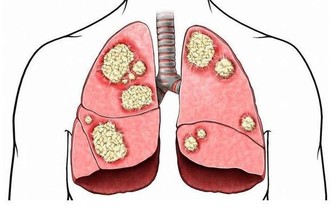

5、乳腺增生

乳腺增生髮生在25~40歲的女性身上,月經前乳房有明顯的脹痛感,月經後即可消失,且有腫塊。期間要保持積極樂觀的情緒,不能過於暴躁,保持規律作息,定期去醫院做檢查。如果發現有腫塊要立即通過手術治療,保持清淡飲食,避免用含有雌性激素的藥物。